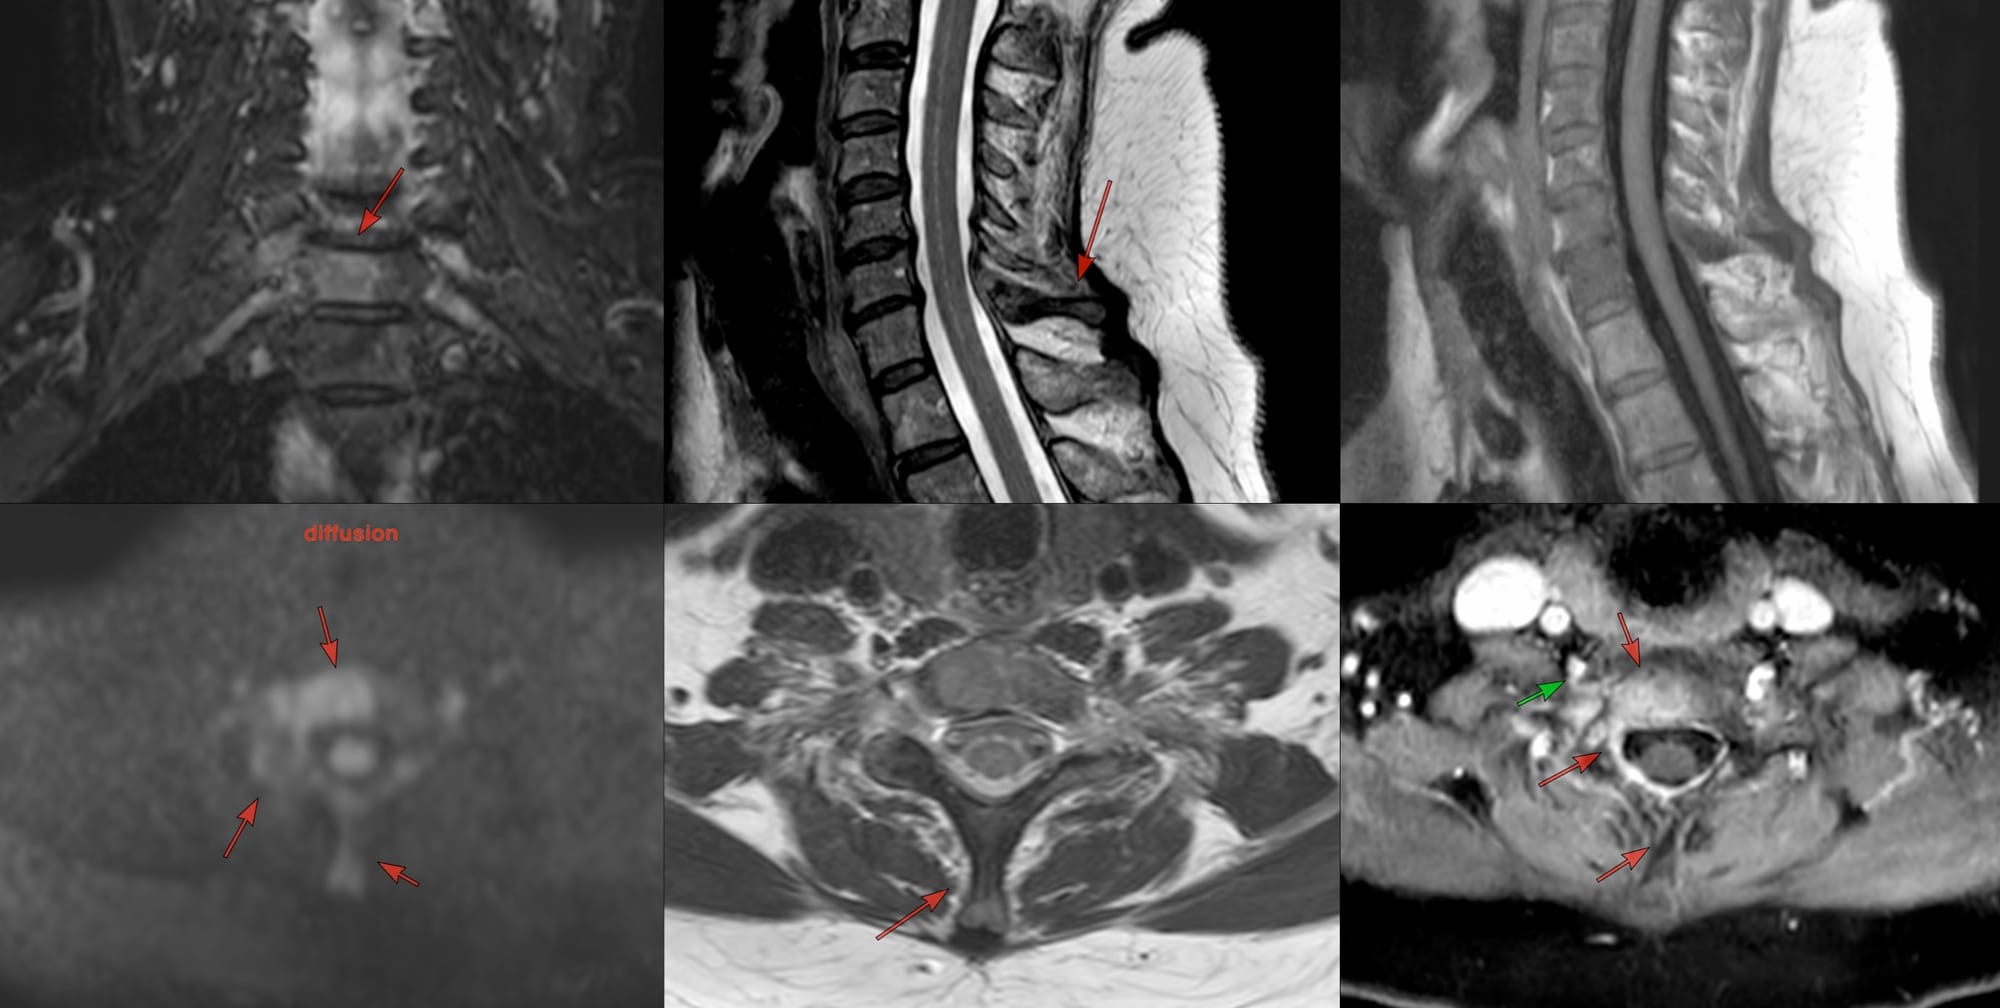

A 60-year old presented with a C7 body lesion on PET, confirmed on MRI.

She was referred for a biopsy.

Do you go anterior? Posterior? What route do you take and why? Which one do you choose from the standard routes available?

The video describes the case and the rationale behind using the transpedicular route in her case.